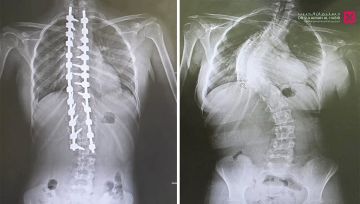

أجرى مستشفى الدكتور سليمان الحبيب بالقصيم، عملية جراحية معقدة، لتقويم انحراف متزايد في العمود الفقري 'جنف'، وتثبيت ودمج الفقرات لفتاة، وأنهت العملية التي استمرت '7' ساعات، معاناة المراجعة مع عدة أعراض حادة استمرت معها لفترة طويلة، وقاد الفريق الطبي المعالج د.ناجي مسعود استشاري جراحة المخ والأعصاب والعمود الفقري ود. صلاح الدين خليفة استشاري جراحة العظام والعمود الفقري.

حيث جاءت المراجعة إلى المستشفى وهي تشتكي من تحدب وإنحاء جانبي، وآلام حادة ومزمنة في الظهر، وغيرها من الأعراض التي تسببت مجتمعة في الحد من حركتها، وقدرتها على ممارستها حياتها بشكل طبيعي، وعقب وصولها إلى المستشفى تم إخضاعها للفحوصات المخبرية وأشعة الرنين المغناطيسي Mri والأشعة السينية X- ray لكامل منطقة الظهر، حيث أكدت النتائج وجود انحراف مزدوج وحاد بزاوية '95' درجة، وأخضعها الفريق الطبي لعملية جراحية، تم فيها تقويم العمود الفقري باستخدام البراغي والقضبان المعدنية، وتثبيت ودمج الفقرات، واستخدمت في العملية، مجموعة من أحدث الأجهزة الطبية منها الجراحة الملاحية Spinal Navigation Surgery، الميكروسكوب Pantero ومراقبة الأعصاب electrophysiology والتي ساهمت في إنجاح التدخل الطبي.

وحولت المراجعة بمؤشرات حيوية مستقرة إلى العناية المركزة ووضعت تحت المراقبة لمدة '24' ساعة ومن ثم نقلت إلى غرفة التنويم وتحسنت حالتها من العناية الطبية الحثيثة، حيث تمكنت من المشي بعد '24' ساعة من العملية تحت إشراف اختصاصي العلاج الطبيعي، ومن ثم غادرت إلى منزلها بحالة صحية ونفسية ممتازة بعد '5' أيام من العملية، وأكدت فحوصات ما بعد العملية أن الميلان تم تعديله بنسبة تفوق الـ'98%' مع الحفاظ على سلامة الأعصاب، إضافة إلى أنها استعادت القدرة على الحركة والمشي بتوازن، والاستلقاء والنوم على ظهرها، فضلاً عن القوام والمظهر الطبيعي، بعد تعديل وضعية الحوض والكتف، كما أن طولها مع النجاح الكبير للتعديل زاد.